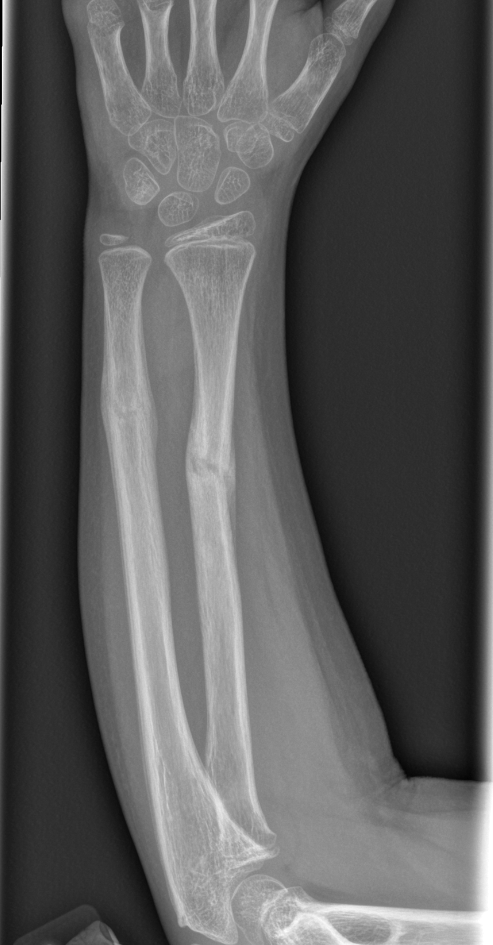

Findings

Bone

Growth plates, ossification centers, apophyses

Joints and alignment